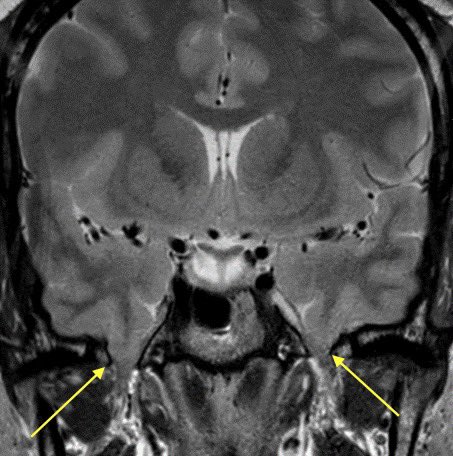

3️⃣Meningoencephaloceles: increased pressure pushes the meninges and brain through spaces they normally should not go. Here is an example of encephaloceles extending through the b/l foramen ovale 2/2 IIH